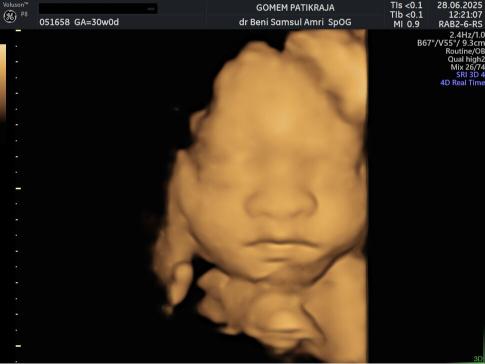

USG Janin 30 Minggu

USG di trimester ke-3 sangat penting untuk memantau posisi bayi, volume air ketuban, and fungsi plasenta. Pastikan janin dalam posisi kepala di bawah dan tidak ada lilitan tali pusat yang mengganggu pergerakannya.